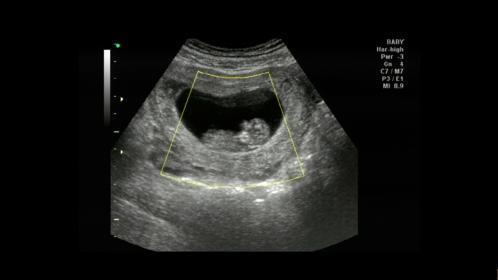

Is it too early for skull guesses?

Skull looks kind of girly.